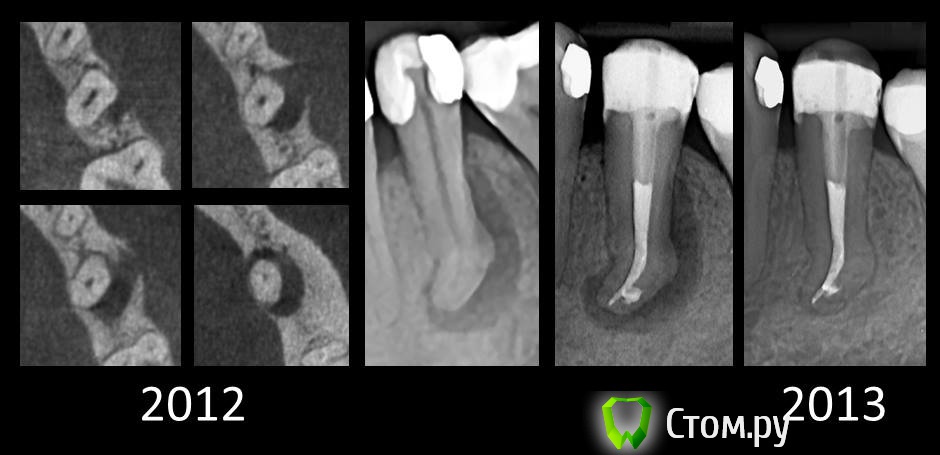

Ico Опубликовано 5 декабря, 2013 Поделиться Опубликовано 5 декабря, 2013 С феисбука фотка 4 Ссылка на комментарий

Kivilgar Опубликовано 5 декабря, 2013 Поделиться Опубликовано 5 декабря, 2013 С феисбука фоткаЗдорово получилось, а кто автор? Ссылка на комментарий

ger_berra Опубликовано 5 декабря, 2013 Автор Поделиться Опубликовано 5 декабря, 2013 Здорово получилось, а кто автор?Mircea Tudericiu 2 Ссылка на комментарий